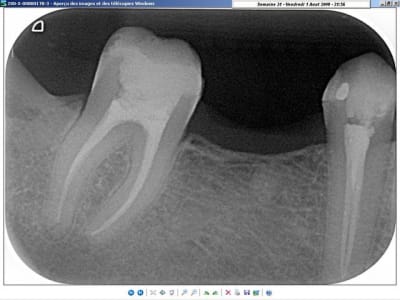

sur ce coup, j'étais bien content d'avoir le thermafill (en prêt)!

38 thermafill wsijl0 - Eugenol

j'ai préféré faire l'endo plutôt que de galérer à la virer... ^^